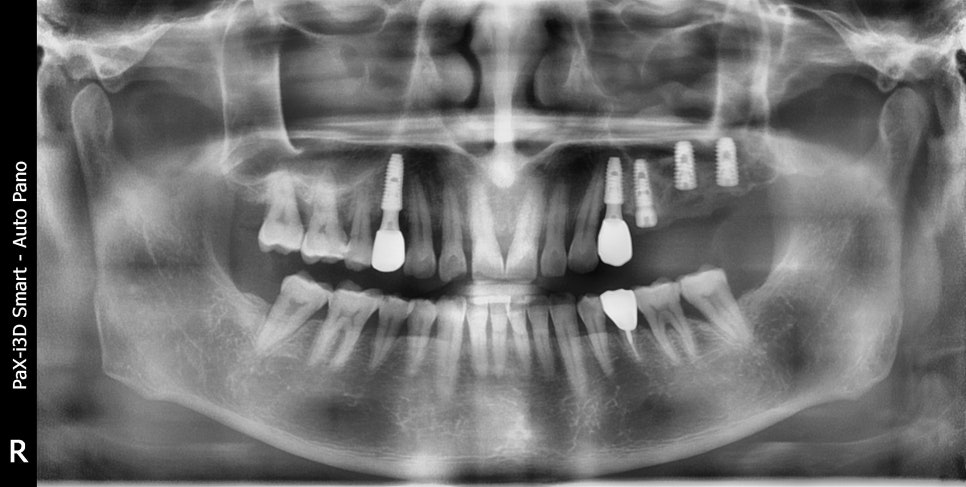

촬영일:2025.02.17(임플란트 3개 식립)

/ 2025.06.30 / 2025.07.11